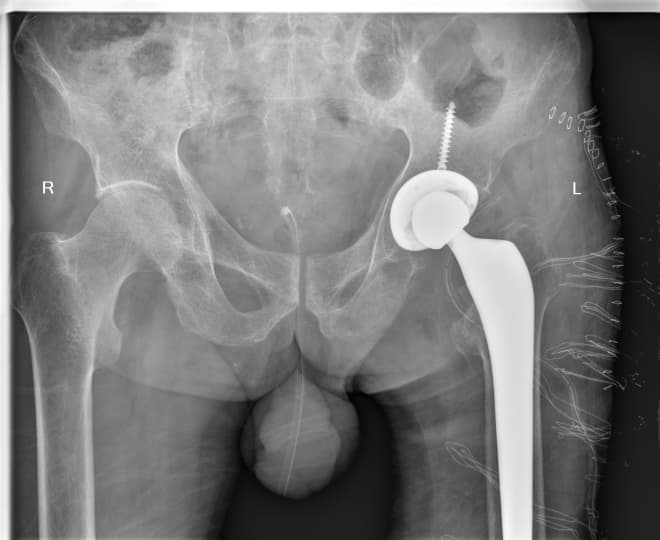

Мэс заслын өмнөх болон дараах рентген зураг

Түнхний үе солих мэс засал гэж юу вэ image16Түнхний үе солих мэс засал гэж юу вэ image17